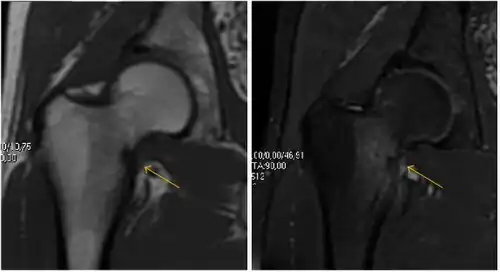

Most of the angles and measurements described in the plain radiograph section can be accurately reproduced on MRI. In addition, the superiority of MRI resolution with intra-articular contrast allows detection of labral and chondral abnormalities that may influence the choice of medical, percutaneous, or surgical management (Figure 9).[1]

Figure 9:

Sagittal T1 weighted image showing anterosuperior labral tear.[1] -

Sagittal T1 weighted image showing chondral lesion.[1] -

Sagittal CT-arthrography showing posteroinferior chondral injury.[1] -

Coronal CT-arthrography (d) showing ligamentum teres tear.[1]

MR arthrography has proven superior in accuracy when compared to native MR imaging. It is considered the best technique to assess the labrum. Knowledge of the normal variable morphology of the labrum helps to differentiate tears from normal variants. A triangular shape is most commonly seen in 66% of asymptomatic volunteers, but round, flattened, and absent labra can also be found in asymptomatic populations. MR arthrography has demonstrated sensitivity over 90% and specificity close to 100% in detecting labral tears. Loose bodies are demonstrated as filling defects surrounded by the hyperintense gadolinium.[1]

Association between labral tears and chondral damage has been demonstrated. This underscores the interaction between cartilage and labrum damage in the progression of osteoarthritis. Chondral damage to the posteroinferior part of the acetabulum as a contrecoup lesion occurs in approximately one-third of pincer cases secondary to persistent abutment on the anterior part of the joint leading to a slight posteroinferior subluxation. This is considered a bad prognosis sign.[1]

MR arthrography can also demonstrate ligamentum teres rupture or capsular laxity, which are debated causes of microinstability of the hip. Elongation of the capsule or injury to the iliofemoral ligament or labrum may be secondary to microtrauma in athletes. MR can demonstrate abnormalities in these cases, such as increased joint volume or a ligamentum teres tear (Figure 9).[1]